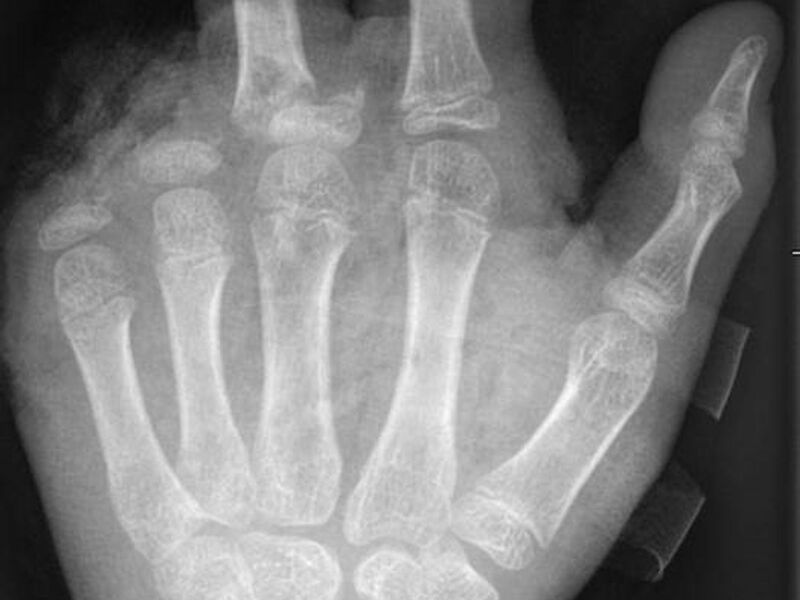

Abgetrennte Finger, durchtrennte Sehnen, Amputationen - die Handchirurgin Leila Harhaus-Wähner hat in der Silvesternacht schon vieles gesehen. Auch in diesem Jahr rechnet die Berliner Ärztin mit zahlreichen Böller-Verletzten. «Für Handchirurgen ist es klar, dass Silvester die arbeitsreichste Nacht sein kann.» Bis 24 Uhr passiere erstmal nicht so viel, ab 1 Uhr, 2 Uhr nachts kämen immer mehr Verletzte in die Notaufnahme und dann «sehr viele in sehr kurzer Zeit.»

In der Handchirurgie müssten an Silvester im Unfallkrankenhaus rund 20 bis 40 Menschen mit Böllerverletzungen operiert werden, sagt die Ärztin. Dieses Jahr werde sie mir vier weiteren Handchirurgen im Einsatz sein. Die häufigsten Verletzungen entstünden durch explodierende Böller in der Hand.

«Der überwiegende Teil der Verletzungen trägt tatsächlich lebenslange Folgen mit sich, weil die Sprengkraft dazu führt, dass eben nicht nur einzelne Strukturen verletzt sind, sondern immer mehrere. Und das heilt praktisch nie ganz folgenlos ab.» Zum Teil könnten Hände nicht mehr gerettet und müssten amputiert werden.

Für eine neue Dimension habe im vergangenen Jahr das illegale Abbrennen von Kugelbomben gesorgt. «Die Patienten mit Verletzungen durch Kugelbomben weisen sehr viel stärkere Verletzungsmuster auf, die auch den ganzen Körper betreffen, weil diese Explosion ungerichtet stattfindet. Und das sind nicht nur Hände und Gesichter, sondern auch Bauch, Beine.» Alle Körperareale seien gleichermaßen gefährdet.